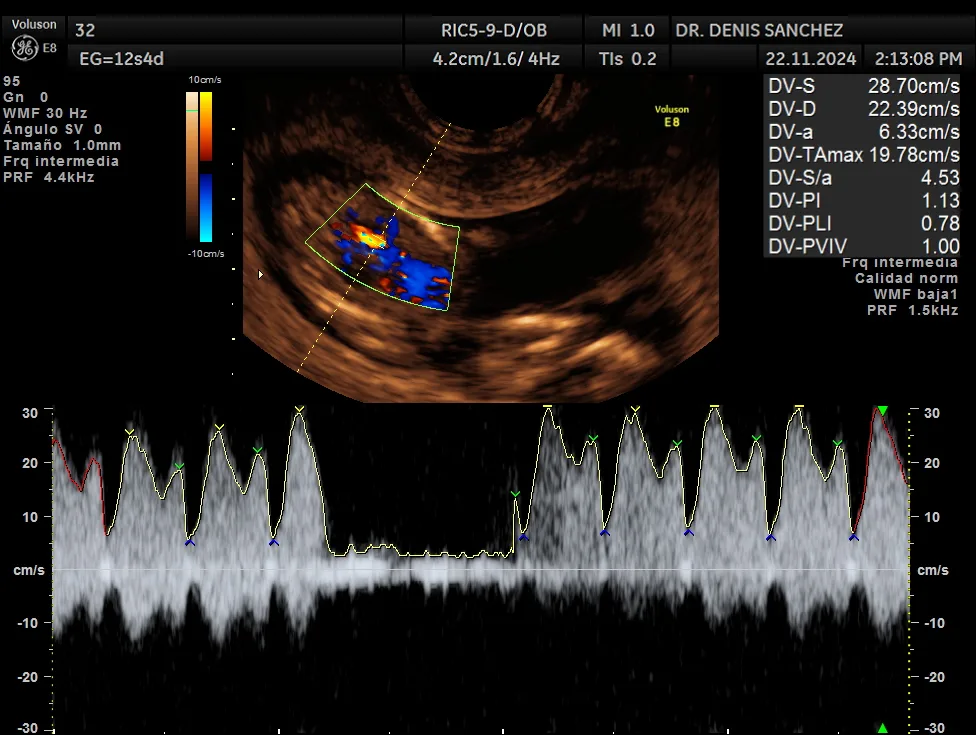

Ecografía Doppler Obstétrica

La técnica especial de ecografía Doppler permite analizar la circulación sanguínea tanto del feto como de la placenta. Esta técnica es especialmente útil en situaciones como hipertensión arterial, diabetes materna, retraso de crecimiento intrauterino y gestaciones generales. La decisión de llevar a cabo este estudio dependerá del ginecólogo responsable de la gestación, quien evaluará su conveniencia de acuerdo con las circunstancias específicas de cada caso.

La ecografía cromosómica, también conocida como tamizaje ecográfico del primer trimestre, se realiza entre las semanas 11 y 14. Evalúa marcadores como el pliegue nucal, el hueso nasal y el flujo del ductus venoso, que pueden indicar riesgo de alteraciones cromosómicas como el síndrome de Down.